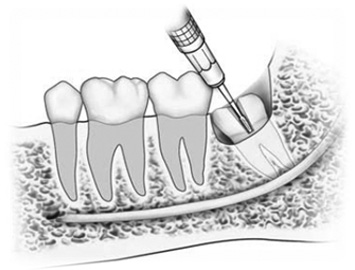

Procedure of removal of Impacted Lower Wisdom Tooth

Many people don’t have enough ‘space’ in the jaws for the wisdom teeth to erupt into a proper, healthy position. This results in misaligned wisdom teeth that is partially erupted through the gums, or not erupted at all.

Impacted tooth may not cause problems for some peopleand may never require treatment. Teeth which are symptomatic may require removal and this usually relieves the symptoms. It is often preferable to have wisdom tooth removed at a younger age as the bone is softer allowing easier extraction and better healing.